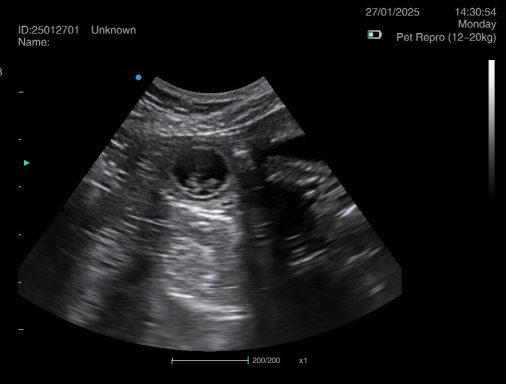

Pregnancy ultrasound scanning - Our pregnancy ultrasound service provides safe, non-invasive confirmation of pregnancy in both dogs and cats. Using advanced scanning technology and gentle handling techniques, we deliver clear, reliable results while prioritizing your pet’s comfort and wellbeing.Whether you visit our calm, home-based clinic or book a mobile appointment, we tailor each session to suit your pet’s needs—supporting responsible breeding with compassion, precision, and care.

Ultrasound pregnancy scanning is a safe, non-invasive way to confirm pregnancy in dogs and cats, offering breeders and pet owners peace of mind and vital information to support responsible care. It allows us to detect gestational sacs, assess foetal development, and estimate litter size—all while ensuring the wellbeing of the animal.

Pregnancy can sometimes be detected as early as Day 18 post-mating, but scanning at this stage is not routinely recommended. Embryos are still developing and may not be clearly visible, and there is a natural risk of embryo resorption, which can lead to misleading or inconclusive results.

For the most accurate and reliable scan, we advise booking between Day 25 and Day 32, when pregnancy is more easily confirmed and foetal structures are clearer. If an early scan is performed and no pregnancy is detected, we offer a FREE complimentary re-scan after 7 days at the clinic to ensure clarity and support informed decision-making.

Our approach balances early insight with ethical care—always prioritizing the comfort of the animal and the accuracy of the results.